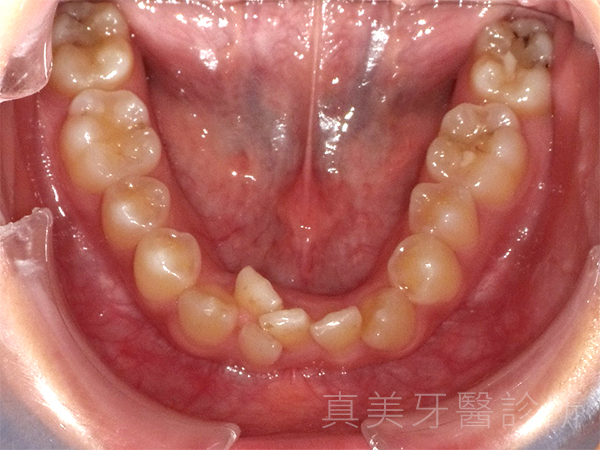

洪小姐是一位學生,平時很喜歡和同學一起參與社團活動,也常需要上台報告或參加課堂討論。對她而言,自信的笑容不只是人際互動的加分,更是展現青春活力的重要部分。不過,她一直對自己的牙齒不太滿意:正中門牙略微內凹、側門牙有些外凸,牙弓也偏狹窄,使得笑容看起來不夠自然,清潔上也較為不便。久而久之,她開始變得不太敢在合照時大方露齒微笑。

經過療程後,洪小姐的牙齒排列整齊了許多,原本外凸的門牙消失了,牙弓也變得更寬更自然。她開心地說,現在不但更喜歡照鏡子,也在合照時勇敢露齒微笑,甚至開始更積極參與各種社交場合。